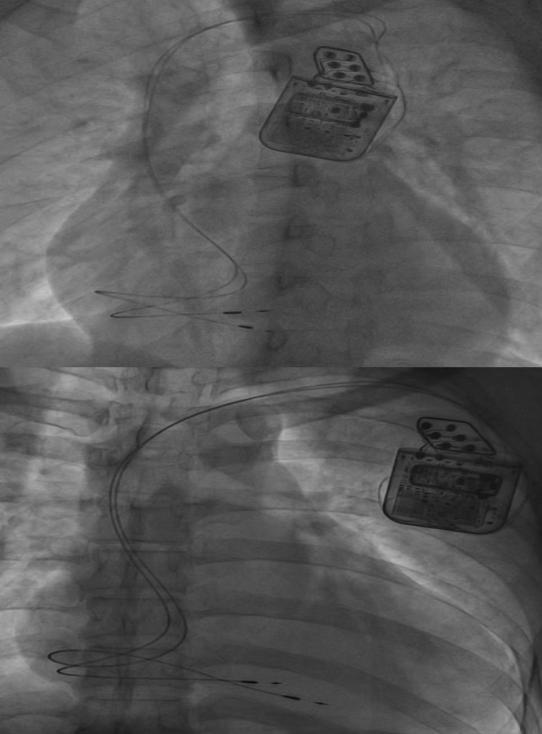

IMG_8047

圖為CCM植入圖)